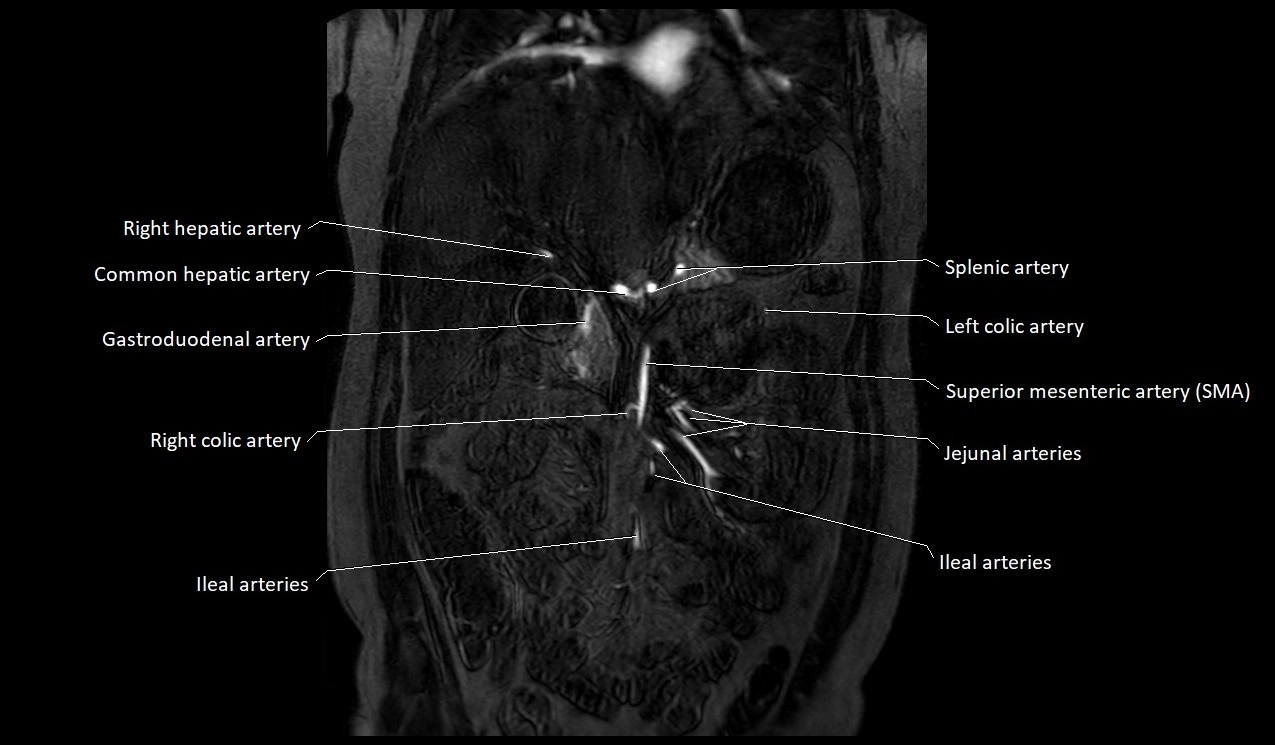

MRI Appearance

T1-weighted images:

Artery appears as a small linear hypointense flow void coursing over the superior pubic ramus

Seen within bright perivascular fat of pelvis

T2-weighted images:

Artery lumen is a signal void

In thrombosed or diseased variants, lumen may appear hyperintense relative to surrounding fat

STIR:

Fat suppression makes the artery more visible within pelvic fat

Helps identify perivascular edema, hematoma, or inflammatory changes

T1 Post-Gadolinium (with fat suppression):

Artery enhances brightly and homogeneously

Useful for tracing the course, anastomoses, and presence of corona mortis

Highlights arterial wall thickening or tumor encasement if present

MRA Pelvis with Gadolinium:

Clearly delineates the origin, course, and anastomoses of the accessory obturator artery

Identifies connection with inferior epigastric artery, external iliac artery, or obturator artery

Excellent for detecting vascular variants prior to surgery

Useful in mapping pelvic vasculature in trauma, tumor embolization, or preoperative planning